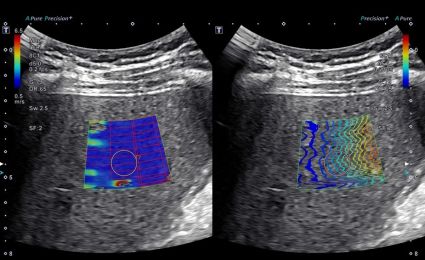

Liver disease is often called a “silent disease” because it can go unnoticed for years, until the damage is done. Elastography is a safe, painless ultrasound to check liver stiffness. It works by sending gentle pulses (called shear waves) through your liver, then tracks how fast they move. The faster they travel, the stiffer and possibly more damaged your liver may be. This helps spot early signs of scarring (fibrosis) before it turns into something more serious, like cirrhosis or liver failure. You may need this exam if your doctor suspects liver disease or wants to monitor your liver without a biopsy. Elastography can also help guide treatment plans and be part of your annual wellness screening.